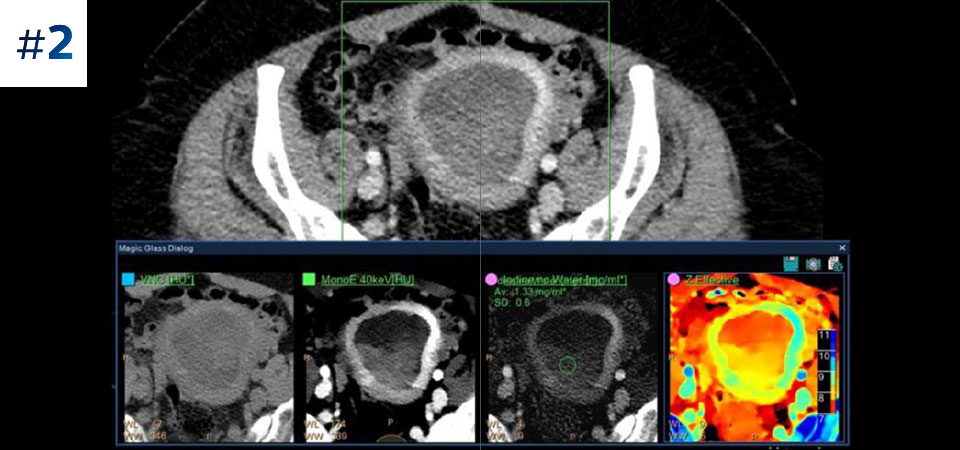

Go beyond conventional CT. See how layers of spectral-detector results can enhance your diagnostic confidence.

Reduced follow-up exams Improved tissue characterization and visualization may reduce the need for follow-up scanning for sub-optimal exams and incidental findings.